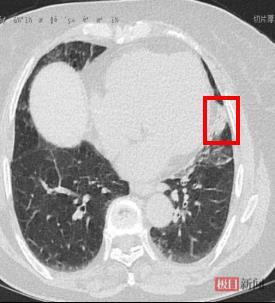

患者术后胸部CT可见瘤体明显缩小,肺不张好转

术后仅1周,长期困扰赵婆婆的胸闷症状就消失了。术后1个月复查胸部CT,赵婆婆肺部肿瘤体积显著缩小,因肿瘤压迫阻塞而塌陷的肺组织也基本复张了。